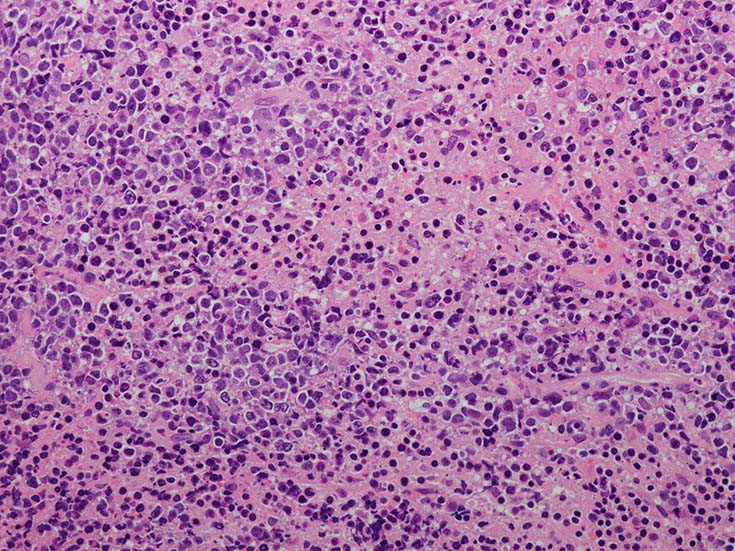

• 組織学的に,LyGは,様々な割合のリンパ球と大きなEBV+芽球からなる血管中心の浸潤を特徴としており,その中にはHRSに類似した特徴を示すものが出現する. 血管浸潤とそれに伴う多量の凝固壊死が典型的な所見である.

血管周囲性に大型類円形核や不整形核をもつ腫瘍細胞がシート状密に浸潤増殖している. Mitosisが多く認められる.細血管閉塞や破壊の所見がある.

間質にもシート状の腫瘍細胞浸潤がある. 大小 pleomorphicな傾向.(A, B). necrosisが認められる(C). 細気管支上皮直下まで密な浸潤あり, 小型リンパ球が混在している.(D)

血管中心性浸潤. 障害された血管内に血栓が形成されている.CD20陽性細胞がシート状密に浸潤, CD3陽性T細胞が多く混在している. EBER-ISH陽性 EBV感染細胞が多数認められ, >50 hpf, 定義より Grade3となる. 陽性細胞のサイズは大小さまざまであることに注意.